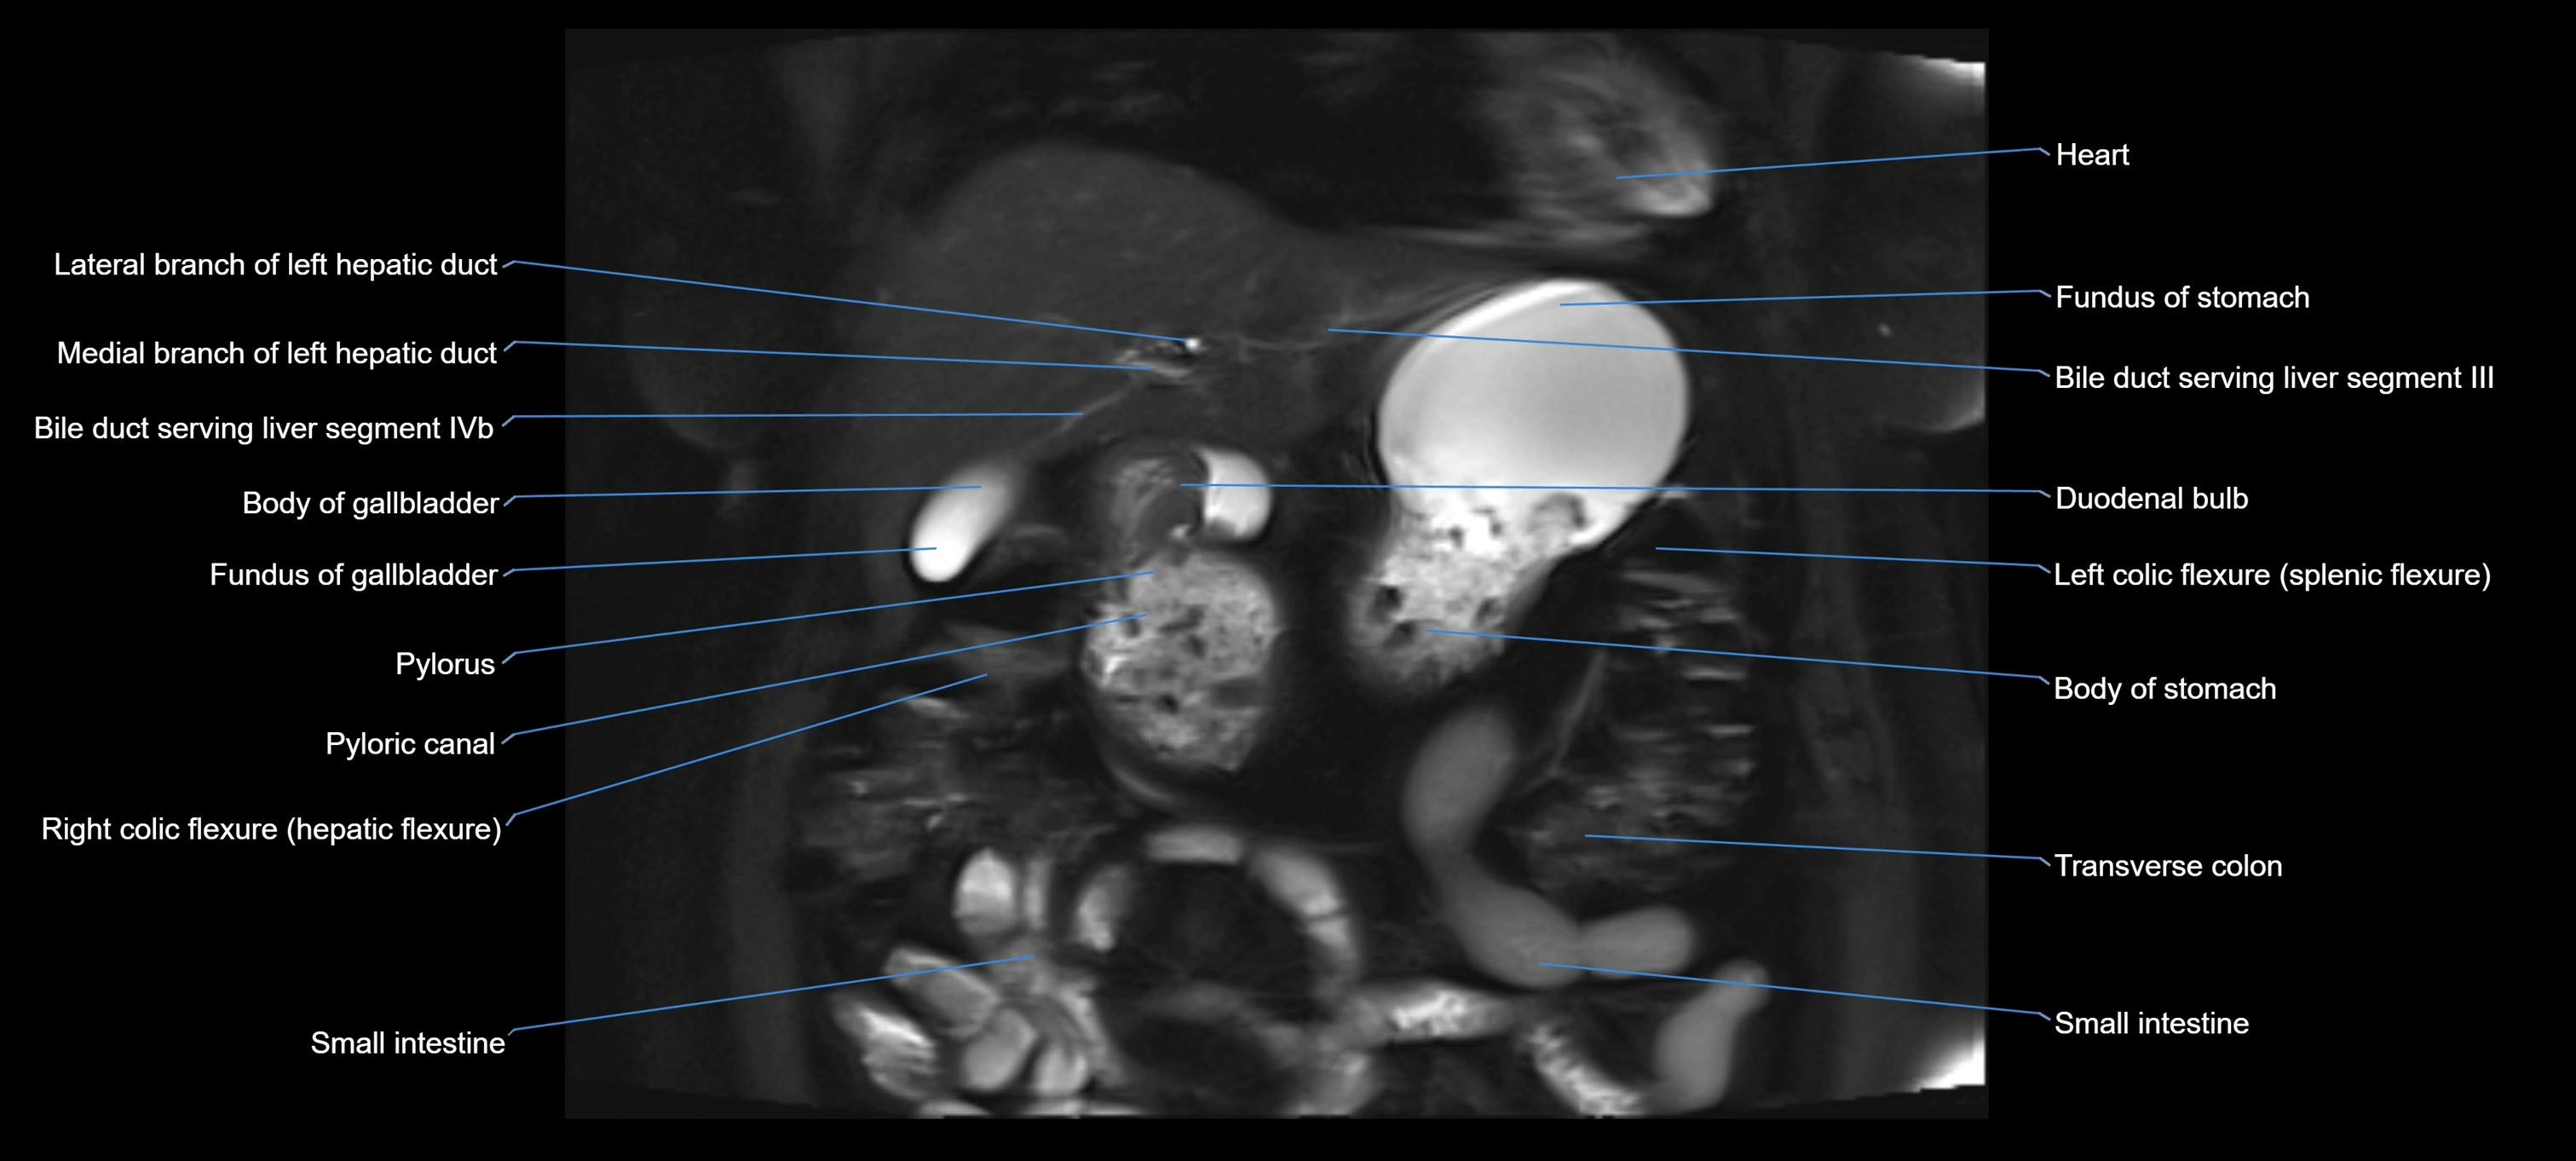

MRI image

image